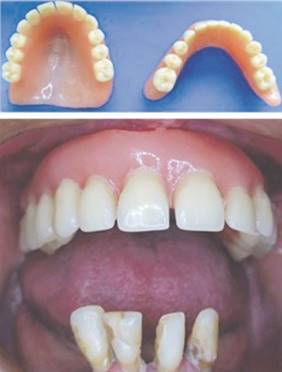

Sobre el modelo de estudio, se cubre el área de RM con tres láminas de cera a fin de espaciar y se confecciona cubeta individual acrílica con mango en el centro palatino (Fig.3 a-b). Los bordes se ajustan en boca a la zona marginal neutra vestibular y al límite palatino posterior con fresón de carbide. Mediante compuesto de modelar (Kerr, USA) se efectúa la impresión de la zona de sellado periférico, sin prolongarlo hacia el área de RM. Con el mismo material se impresiona la zona de sellado principal palatino, extendiéndolo hacia el paladar duro (Fig.3 c).Se comprueba el grado de retención obtenido traccionando la cubeta, la cual debe ejercer resistencia al desalojo. Se perfora la zona anterior y posterior del espaciado con fresa redonda de carbide de 1 milímetro de diámetro y se pincela toda la cubeta con adhesivo para silicona (Coltene, Suiza) (Fig3 d). Se carga la zona posterior y palatina de la cubeta con silicona de polivinilsiloxano de adición (3M, USA) a través de pistola y se asienta y estabiliza en boca mediante el mango central (Fig.4 a). Se introduce la punta aplicadora en los agujeros vestibulares del espaciado rellenando con silicona hasta verificar la salida del exceso de material por los agujeros palatinos; se repite la operación a través de estos últimos (Fig.4 b). Se complementa rellenando por todo el borde vestibular anterior. Durante el tiempo de trabajo del material, se efectúan suaves movimientos rotatorios de labios y mejillas guiados por el operador, a fin de registrar la actividad muscular hasta su polimerización total. Se retira la cubeta de boca, se lava, se critica la impresión, se reposiciona en boca para verificar su retención y estabilidad (Fig.5). Se lava y desinfecta, se encofra y se obtiene el modelo de trabajo sobre el cual se termina la prótesis de manera convencional, dándole un esquema oclusal balanceado bilateral con leve inoclusión del grupo dentario anterior. Se efectúan las exodoncias de los dientes remanentes inferiores, se instalan las prótesis y se realizan controles post-operatorios a fin de verificar el comportamiento de las prótesis, detectar zonas de sobrecompresión y rebasar la prótesis inferior una vez cicatrizados los tejidos (Fig.6).